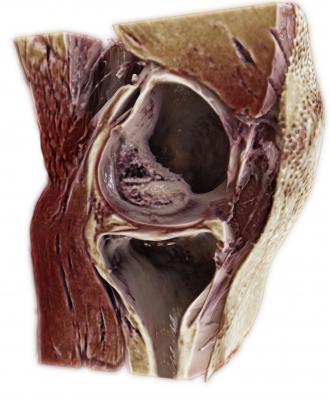

November 27, 2017 — At the 103rd Scientific Assembly and Annual Meeting of the Radiological Society of North America (RSNA), Siemens Healthineers debuted GOKnee3D, a magnetic resonance imaging (MRI) application that drastically shortens the time required to perform comprehensive diagnostic exams of the knee. Currently, a typical knee examination can be roughly 20 minutes. GOKnee3D enables a push-button, high-resolution diagnostic 3-D knee exam in just 10 minutes. The acquisition of high-resolution isotropic 3-D images subsequently allows flexible evaluation of the images in all possible planes, including double oblique and curved planar. Increasing MRI efficiency in this manner is especially important because knee examinations are the third most common type of MRI examination, accounting for 11 percent of all scans.

To develop and clinically validate the technique, Siemens Healthineers collaborated with Johns Hopkins University in Baltimore. “GOKnee3D enables comprehensive evaluation of internal derangement to the knee,” said Jan Fritz, M.D., assistant professor of radiology and radiological sciences at the Johns Hopkins University School of Medicine. “The fully automated CAIPIRINHA SPACE protocol provides high-quality MR imaging in 10 minutes and ensures consistency of image quality and operational efficiency. The high spatial resolution isotropic data sets help to visualize abnormalities with high accuracy, enable reformations of virtually any imaging plane, and create high-quality 3-D-rendered MR images.”